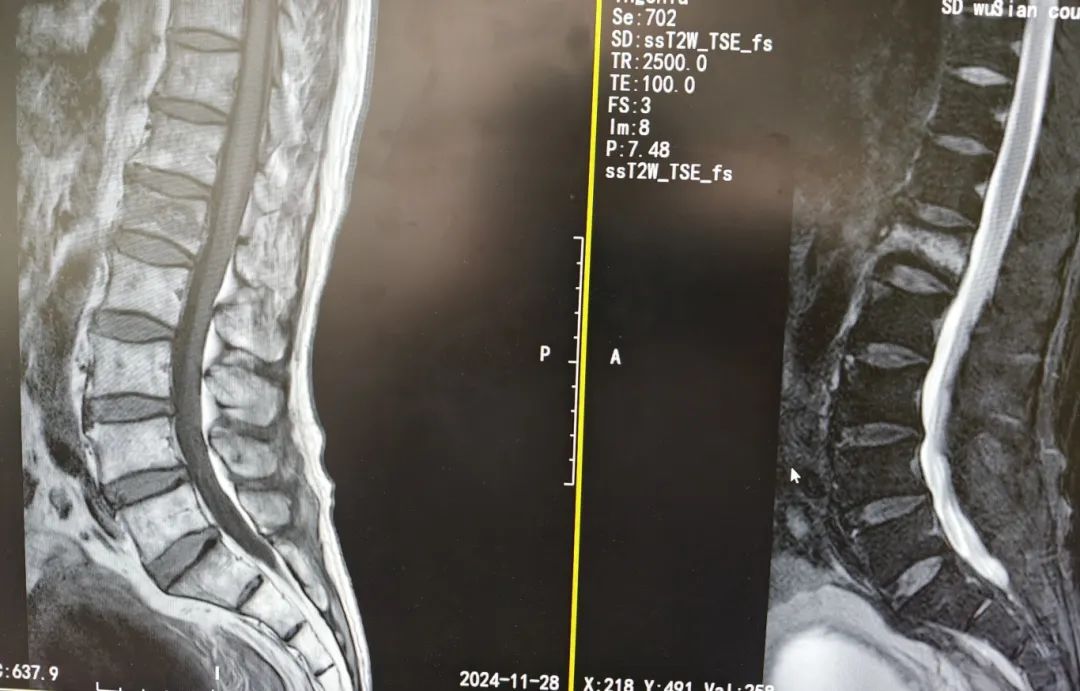

患者自述不慎自家中高处(约2.5m)跌落,后背部及左髋部着地,致使腰背部疼痛难忍,活动明显受限。伤后120急救车紧急接入我院急诊就诊,腰椎椎体CT显示:L1椎体压缩性骨折、L2左侧横突骨折,L1/2椎间盘真空症征。

术前影像

骨科结合病史、查体及影像学检查初步诊断为:1.L1椎体压缩性骨折;2.L2椎体横突骨折。